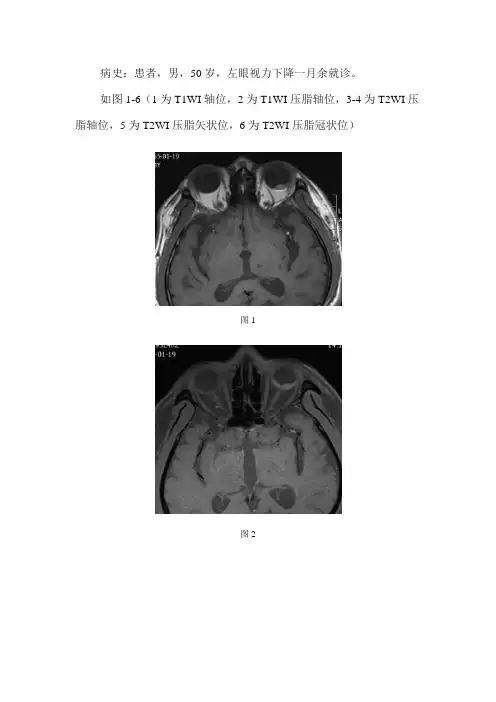

病史:患者,男,50岁,左眼视力下降一月余就诊。

如图1-6(1为T1WI轴位,2为T1WI压脂轴位,3-4为T2WI压脂轴位,5为T2WI压脂矢状位,6为T2WI压脂冠状位)图1图2图3图4图5图6基础解剖影像:以上为眼球内部结构示意图及前外侧视角眼部结构立体示意图。

图1图2图3图4图5图6MRI影像:左眼球后壁偏颞侧及后侧见丘状隆起(黄色箭头),其内见小结节影,T1WI及T1WI压脂像呈稍长信号,T2WI压脂像呈中央稍长、周围低信号,大小约6.3x10.5mm,边界清晰,相邻眼底见条形稍短T1稍短T2信号。

影像诊断:左眼球后壁考虑视网膜剥离合并出血可能。